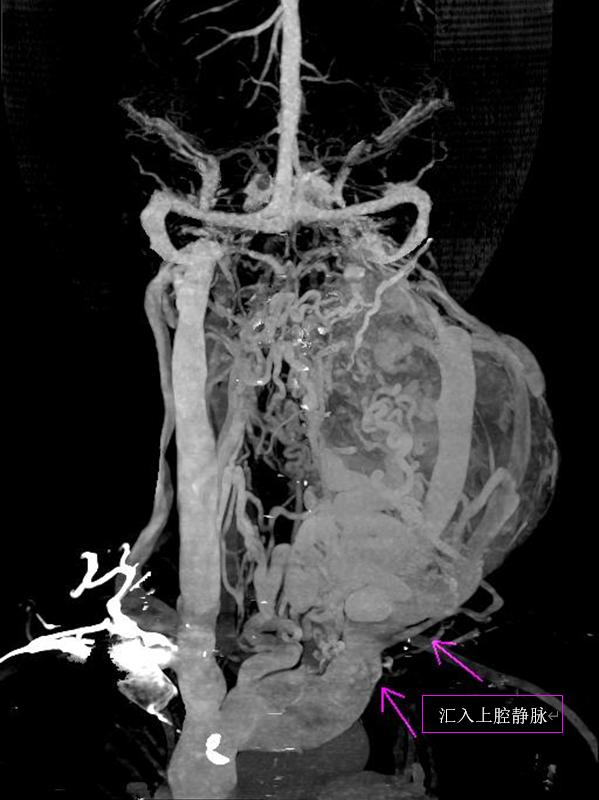

同时在肿块的表面又有许多新生的静脉血管团注入上腔静脉。

随后全景医生将动静脉图像叠加融合后,在西门子Syngo.via医学影像后处理系统(VB20版)处理得到颈部动静脉的CT三维图像,并使用电影级的三维可视化实影渲染技术(cVRT),逼真显示出肿块内动脉与静脉的走行关系与三维结构。

经过一系列后处理,肿块血供解剖信息一目了然。

再进行剖面重建并将动脉静脉标识为不同颜色,直观显示出这个肿块内穿行着颈总动脉,并发出“蔓藤样”迂曲的动脉血管网,表面覆盖着静脉血管团,然后汇入上腔静脉(见下图),诊断呼之欲出,这是一个罕见的左侧颈部巨大血管瘤。